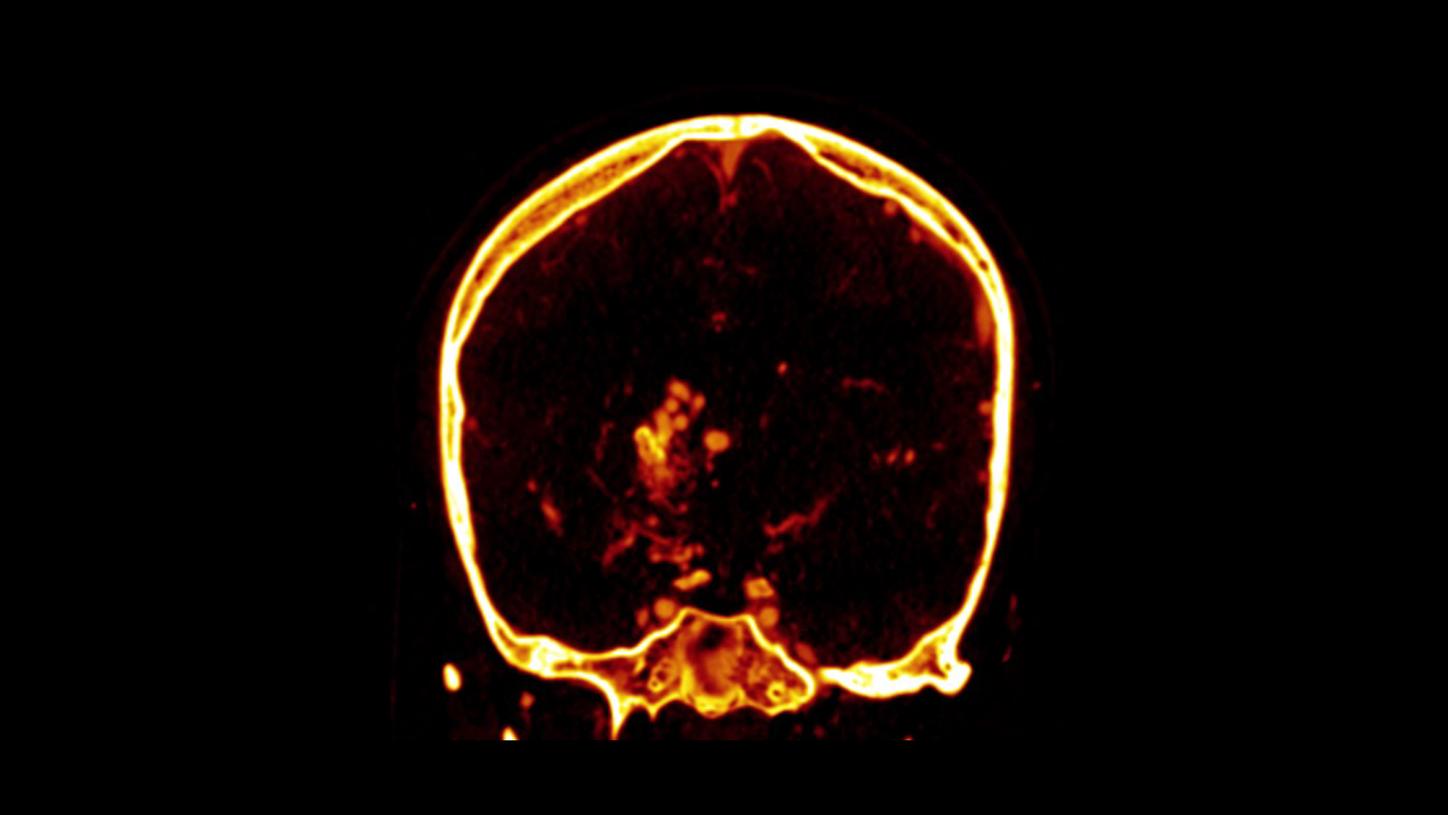

example of hemorrhage visualization

example of hemorrhage visualization

example of hemorrhage visualization